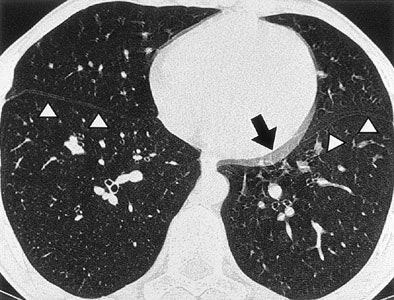

| Tram-track and double cardiac contour artifacts. Non-ECG-gated thin-section CT scans obtained at the same level of the paracardiac parenchyma in a 25-year-old man with spontaneous pneumothorax. Note the double contour artifact seen in the blurred cardiac border (arrow). Tram-track artifacts can be seen in both the right and left interlobar fissures (arrowheads) (Radiology, 1999;212:649-654). |

In a 1999 study, Schoepf and colleagues from the University of Munich in Germany aimed to identify the benefits of prospective ECG triggering for examining the lung parenchyma using high-resolution CT (Radiology, September 1999, Vol. 212:3, pp. 649-654).

"You can see that ECG triggering takes care of those twinkling star artifacts adjacent to the left cardiac border," he said of an image projected on the screen. "You get rid of what has been dubbed the tram-track sign, the double appearance of the (lung) fissures, and the double cardiac border."